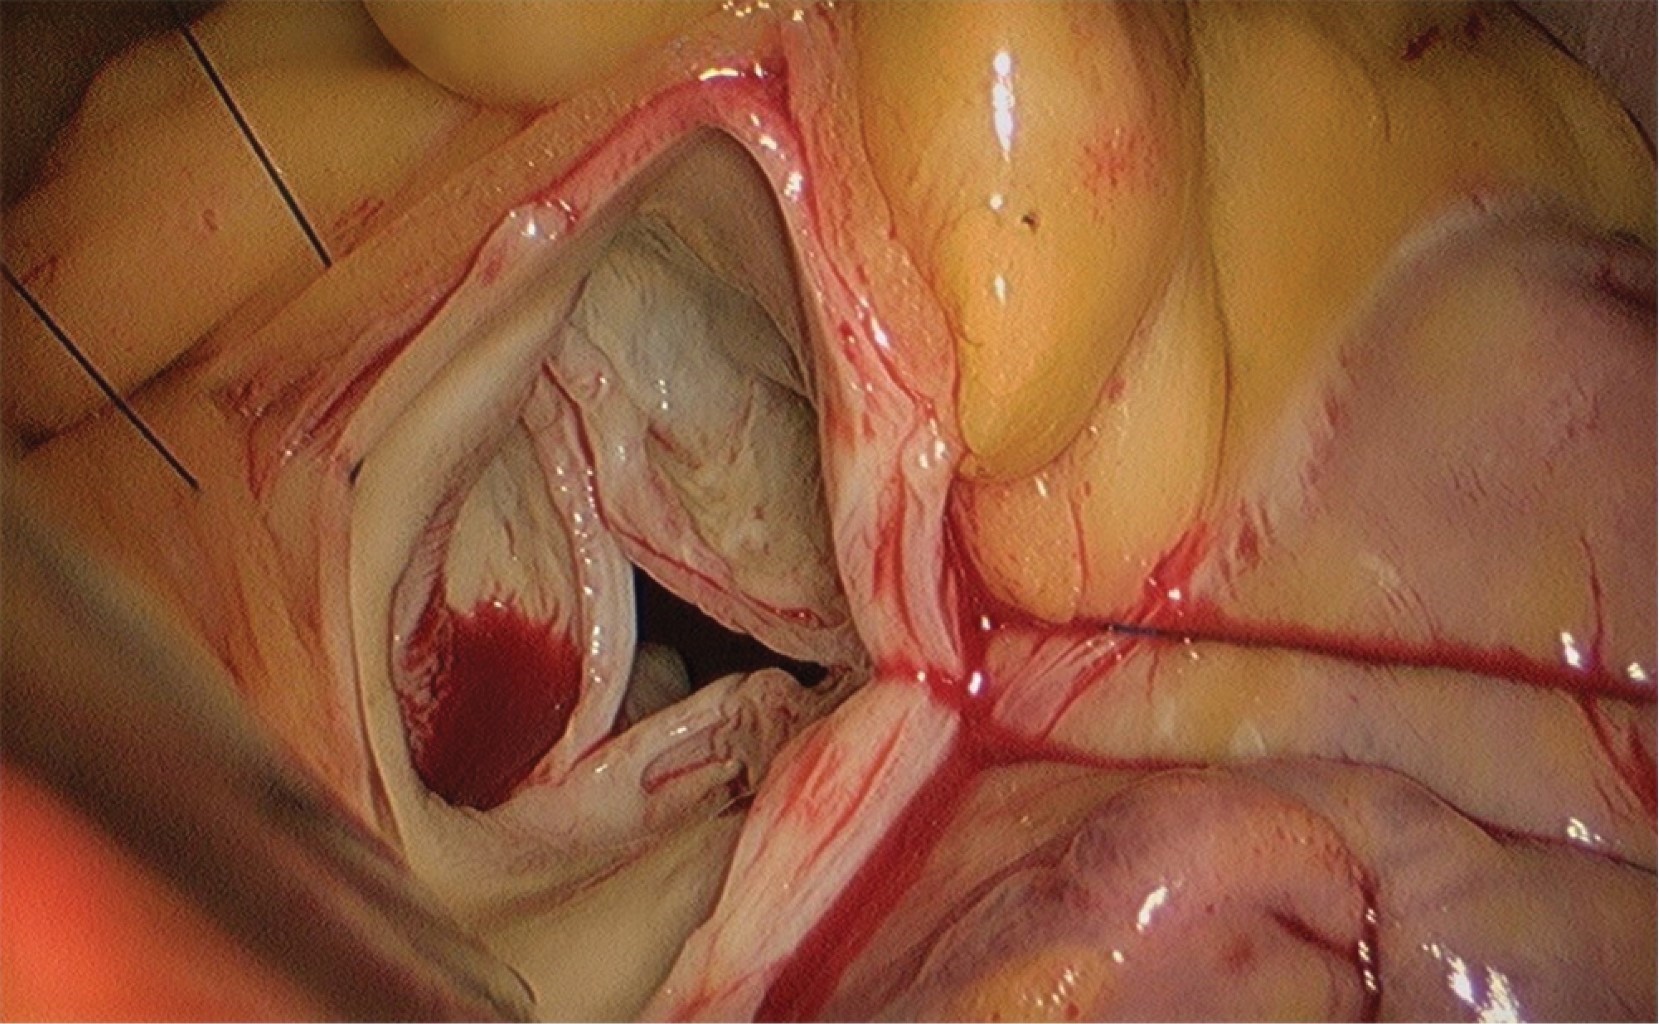

Figura 1